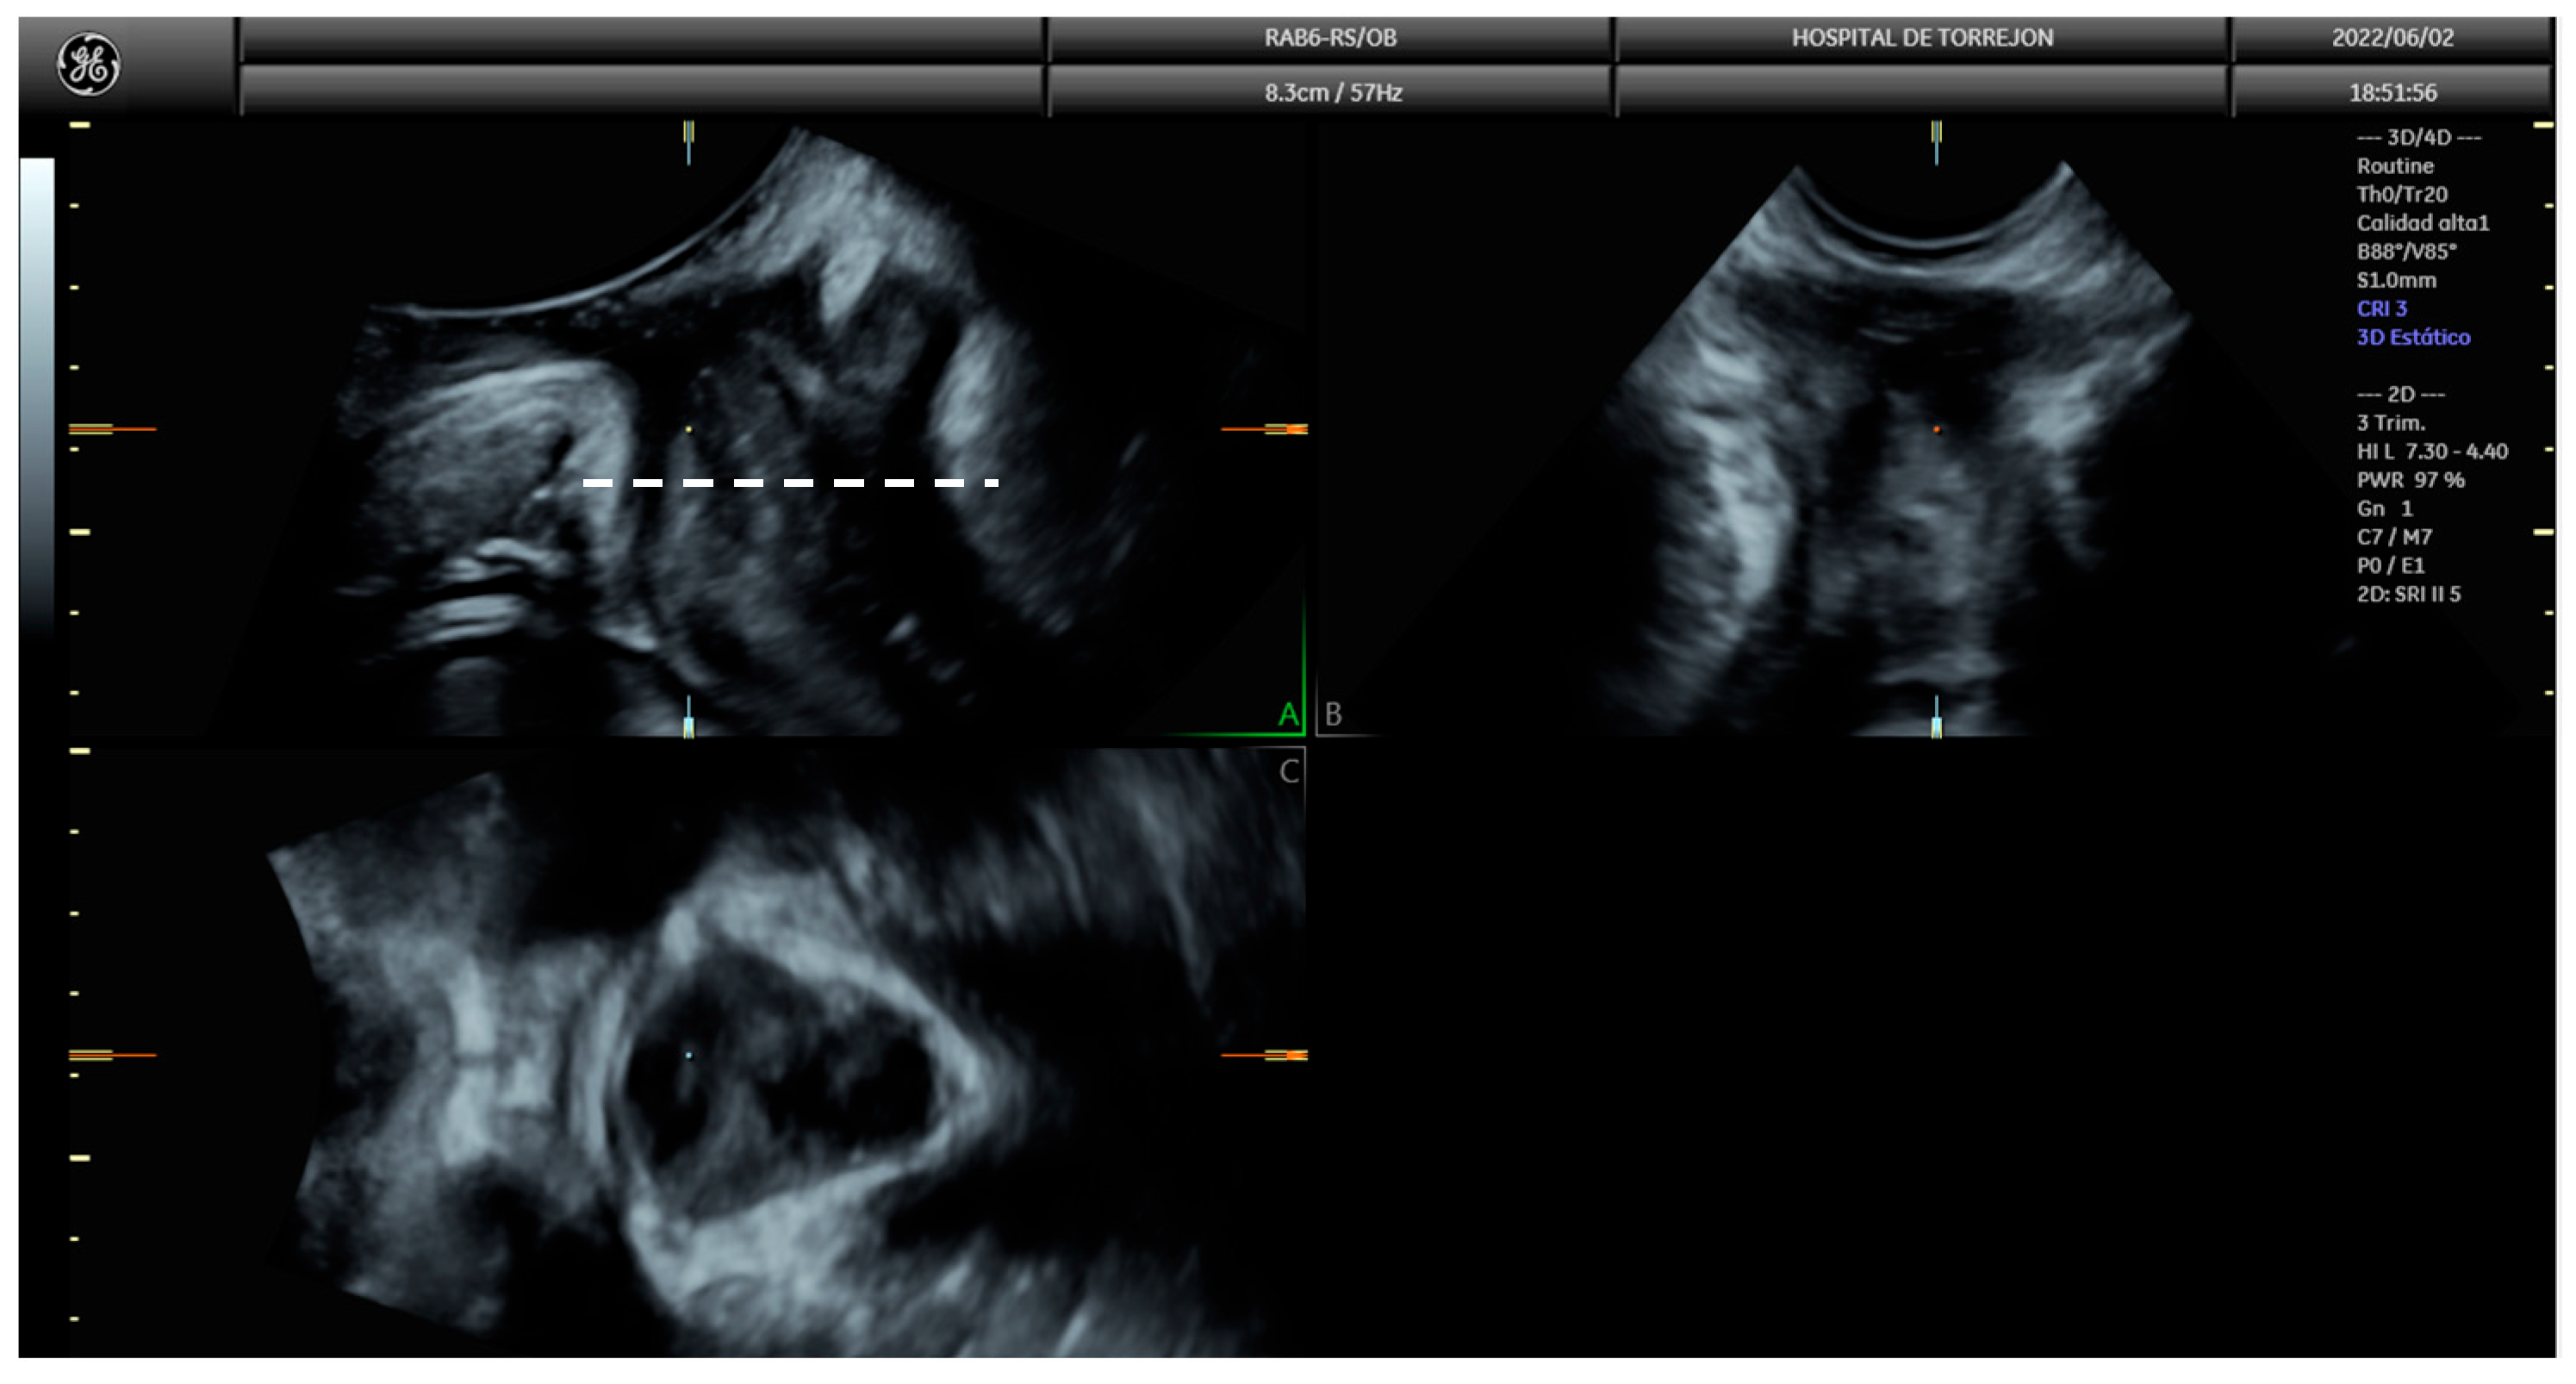

2.6. Pelvic Floor Ultrasound

- Dietz, H.P. Ultrasound imaging of the pelvic floor. Part II: Three-dimensional or volume imaging. Ultrasound Obstet. Gynecol. 2004, 23, 615–625. [Google Scholar] [CrossRef] [PubMed]

- Dietz, H.P.; Shek, K.L. Tomographic ultrasound imaging of the pelvic floor: Which levels matter most? Ultrasound Obstet. Gynecol. 2009, 33, 698–703. [Google Scholar] [CrossRef] [PubMed]